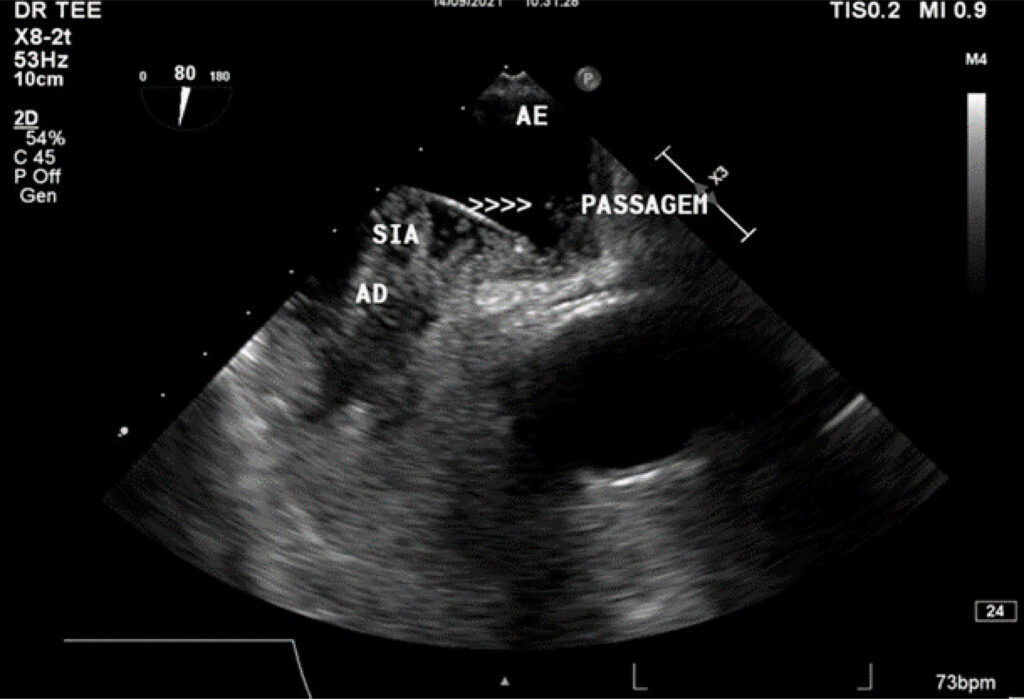

Tromboembolismo Pulmonar Associado com Embolia Paradoxal em um Paciente com Forame Oval Patente

O forame oval patente (FOP) é uma condição clínico-patológica caracterizada por uma abertura na fossa oval, o que permite a passagem de sangue entre os átrios, presente em cerca de 25% da população adulta, na maioria sem repercussões hemodinâmicas. No entanto, devido à patência desse forame, pode ocorrer o embolismo paradoxal como causa de eventos isquêmicos e, em alguns casos, há indicação de fechamento do forame oval como medida de prevenção secundária para eventos tromboembólicos.

Estudos comprovam a associação entre FOP e diversos quadros clínicos, alguns potencialmente graves, tais como acidente vascular encefálico isquêmico (AVEi) e tromboembolismo pulmonar (TEP).